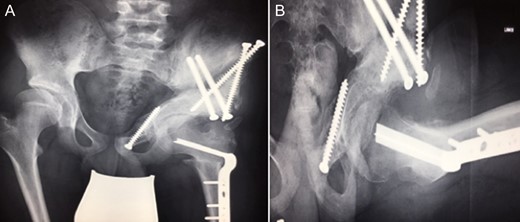

Ten years ago, a 12-year-old male presented to our clinic complaining about limping and massive swelling of the left hip. Figure 1 shows the initial X-ray and the 3D reconstruction of the left hip at first presentation when the femoral head, had already destroyed the lateral edge of the acetabulum like a mortar. Severe pain episodes have apparently not been noticed and a former hip dysplasia was not known. A brief clinical history revealed that the patient presented repeated episodes of finger biting and fevers from 2 to 8 years old. The intelligence level of the patient was at an average. The patient was admitted to a paediatric neurologist and a genetic test. A mutation of the NTRK1 gene was found and the diagnosis of CIPA was established. The right hip initially appeared to be normal and the patient was walking, therefore surgical reconstruction for the left hip was proposed due to massive swelling, inability of normal walking and significant limb length discrepancy. A Tönnis/Kalchschmidt triple pelvic osteotomy with open reduction and a shortening varus derotation osteotomy (VDRO) of the femur was performed (Fig. 2A–B). After 3 months the patient was walking again but another 3 months later the hip dislocated again without severe pain. Although the femoral head was already damaged the hip joint was reconstructed again by open reduction, capsular reconstruction with suture anchors and a trevira tube and a movable external fixator was used to temporary stabilize the joint (Fig. 3). The right hip at this time was still intact and was protected with a pneumatic orthotic device. A few months later in 2009, despite all surgeries, the left hip had entirely lost congruency and the right hip developed subluxation despite conservative treatment (Fig. 4). The patient was still walking so the decision to reconstruct the right hip with open reduction, capsular augmentation with a trevira tube, a triple pelvic osteotomy and VDRO was made (Fig. 5). Few months later this reconstruction failed as well and the hip dislocated without severe pain (Fig. 6).

(A + B): (2008) (A) X-ray of the left hip demonstrating subluxation of the femoral head which is destroying the edge of the acetabulum (arrow) like a mortar. (B) 3-D reconstruction of the hip showing bony debris of the acetabulum edge forming a secondary acetabulum (asterisk) trying to cover the femoral head.